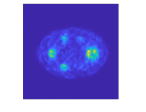

We used the XCAT [44] phantom (Fig. 2) to simulate Y-90 PET following radioembolization. We set the image size to 128128100 with a voxel size 4.04.04.0 (mm3) and chose 100 slices ranging from lung to liver. To simulate extremely low count scans with high random fractions, typical for Y-90 PET, we set total true coincidences and random fractions based on numbers from patient PET imaging performed after radioembolization [45]. To test the generalization capability of the trained BCD-Net, we changed all imaging factors between training and testing dataset. Here, imaging factors include activity distribution (shape and size of tumor and liver background, concentration ratio between hot and warm region) and count-level (total true coincidences and random fraction). Fig. 2 and Table I provide details on how we changed the testing dataset from the training dataset. We trained BCD-Net using five pairs () of 3D true images and estimated images at each iteration (1 true image, 5 realizations). We generated multiple (5) realizations to train the denoising NN to deal with the Poisson noise. We also generated 5 realizations (1 true image, 5 realizations) as a testing dataset to evaluate the noise across realizations.

II-F Evaluation metrics

For the XCAT phantom simulation, we evaluated each reconstruction with contrast recovery (CR) (volume-of-interest (VOI): cold spot indicated in Fig. 2), noise across realizations, root mean squared error (RMSE), and contrast to noise ratio (CNR). For the physical phantom measurement, we used CR (VOI: hot spheres) and CNR averaged over multiple hot spheres. We define each VOI’s mask based on attenuation map interpolated to PET voxel size. For the patient measurement, we used CNR and the field of view (FOV) activity bias since the total activity in FOV is known (equal to the injected activity because the microspheres are trapped) wheareas the activity distribution is unknown:

where is mean counts in the VOI, is true ratio between hot and warm region, denotes the th voxel of an image , is the number of realizations ( in both XCAT phantom simulation and physical phantom measurement) and is the number of voxels in the volume of liver, is standard deviation between voxel values in uniform background liver (indicated in Fig. 2), and is the total number of voxels in the FOV. As the background region when calculating the patient CNR, we used a part of liver region that has relatively uniform activity distribution.

| Attenuation map (coronal) | Attenuation map (axial) | True activity (training) | True activity (testing) | Zoomed in |

|---|---|---|---|---|

![]() |